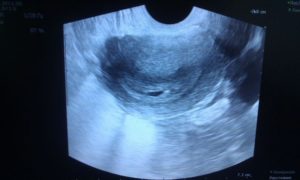

Расшифровкой данных ультразвукового исследования должен заниматься только квалифицированный специалист. На первом УЗИ специалист определяет:

- Наличие каплевидного или округлого гипоэхогенного образования, диаметр которого составляет 0,3-0,5 см. От срока зависит и размер.

- Образование должно быть окружено тонкой оболочкой. Данное образование и есть плодное яйцо.

- Наличие желтого тела.

Во время первого УЗИ обнаруживаются:

- круглое или каплевидное образование с низкой эхогенностью размером 3-5 мм. Его размер определяет срок;

- тонкая оболочка вокруг развивающегося ребёнка;

- жёлтое тело – оно вырабатывает прогестерон, способствующий сохранению плода.